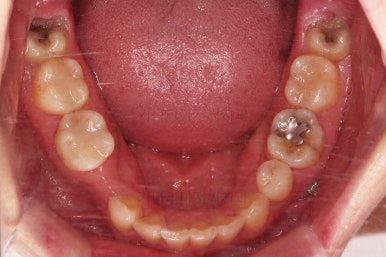

임플란트 보철까지 잘 세팅이 된 후 마무리 하게 되었습니다.

임플란트까지 잘 들어간 후 마무리 했고요.

결손공간 없이 상하좌우 모두 같은 갯수의 치아로 치료가 잘 종료되었습니다.

부산인비절라인 전후 비교해 볼게요.

당연히 빈공간에 대한 처리도 잘 되었고요.

얼굴에 대한 중앙선도 잘 마무리 되었습니다.

어쨌든 모든 부분에서 인비절라인으로 잘 마무리가 된 환자분이었습니다.

이상 결손치아가 5개 있었고, 비대칭, 유치잔존 환자분을 부산인비절라인으로 교정치료 후 임플란트 2개로 마무리를 한 치료사례였습니다.